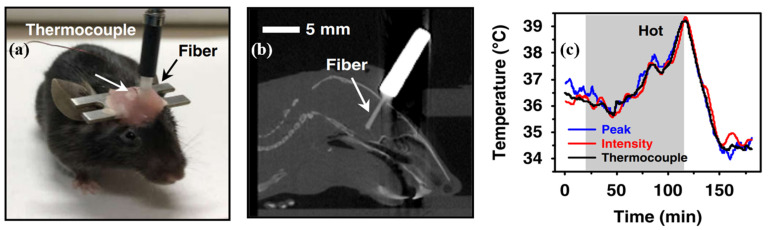

One typical use for optical fibers is in the field of optical detection. OE qualities are necessary for multimaterial fiber photodetectors that are used in medical applications, such as internal observation and imaging. Various semiconductors possess a wide range of characteristics, making semiconductor OE fibers appealing [169]. These characteristics include a broad range of infrared transparency, significant optical nonlinearity, and a high refractive index [66]. All examples of nonlinear behavior in semiconductor optical fibers have been linked with centrosymmetric crystal systems, with the major portion associated with the silicon fiber framework [93]. The transformation of optical power into electrical power is the fundamental process that underpins the majority of semiconductor-detecting or energy-collecting OE devices [170]. This transformation is a significant advantage of the semiconductor OE fiber platform over other similar technologies. Both in-fiber detectors and “solar threads” have been manufactured using this technology to achieve this goal [102,123]. This platform is distinguished from previous fiber technologies by the possibility of incorporating OE functionality into the constituent material of the waveguiding fiber. Moreover, the OE property can be further utilized to detect in vivo temperature, as demonstrated in Figure 7. The fiber-integrated device can measure deep brain temperature variations. Complementary to tethered electrical sensors, this optical-based approach is more appropriate for use in areas with significant electromagnetic interference and is especially capable of acquiring data during magnetic resonance imaging (MRI). As a result, various fiber optic sensors based on OE characteristics, such as the bandgap of a GaAs crystal material [171], have been implemented [172,173].

Figure 7.

OE fiber-integrated devices for in vivo temperature sensing (Reprinted with permission from ref. [180]. Copyright 2022 He Ding et al.): (a) a mouse implanted with a fiber sensor for temperature detection; (b) sagittal CT slice reconstruction; and (c) dynamic temperature data acquired by the fiber sensor in the mouse brain.